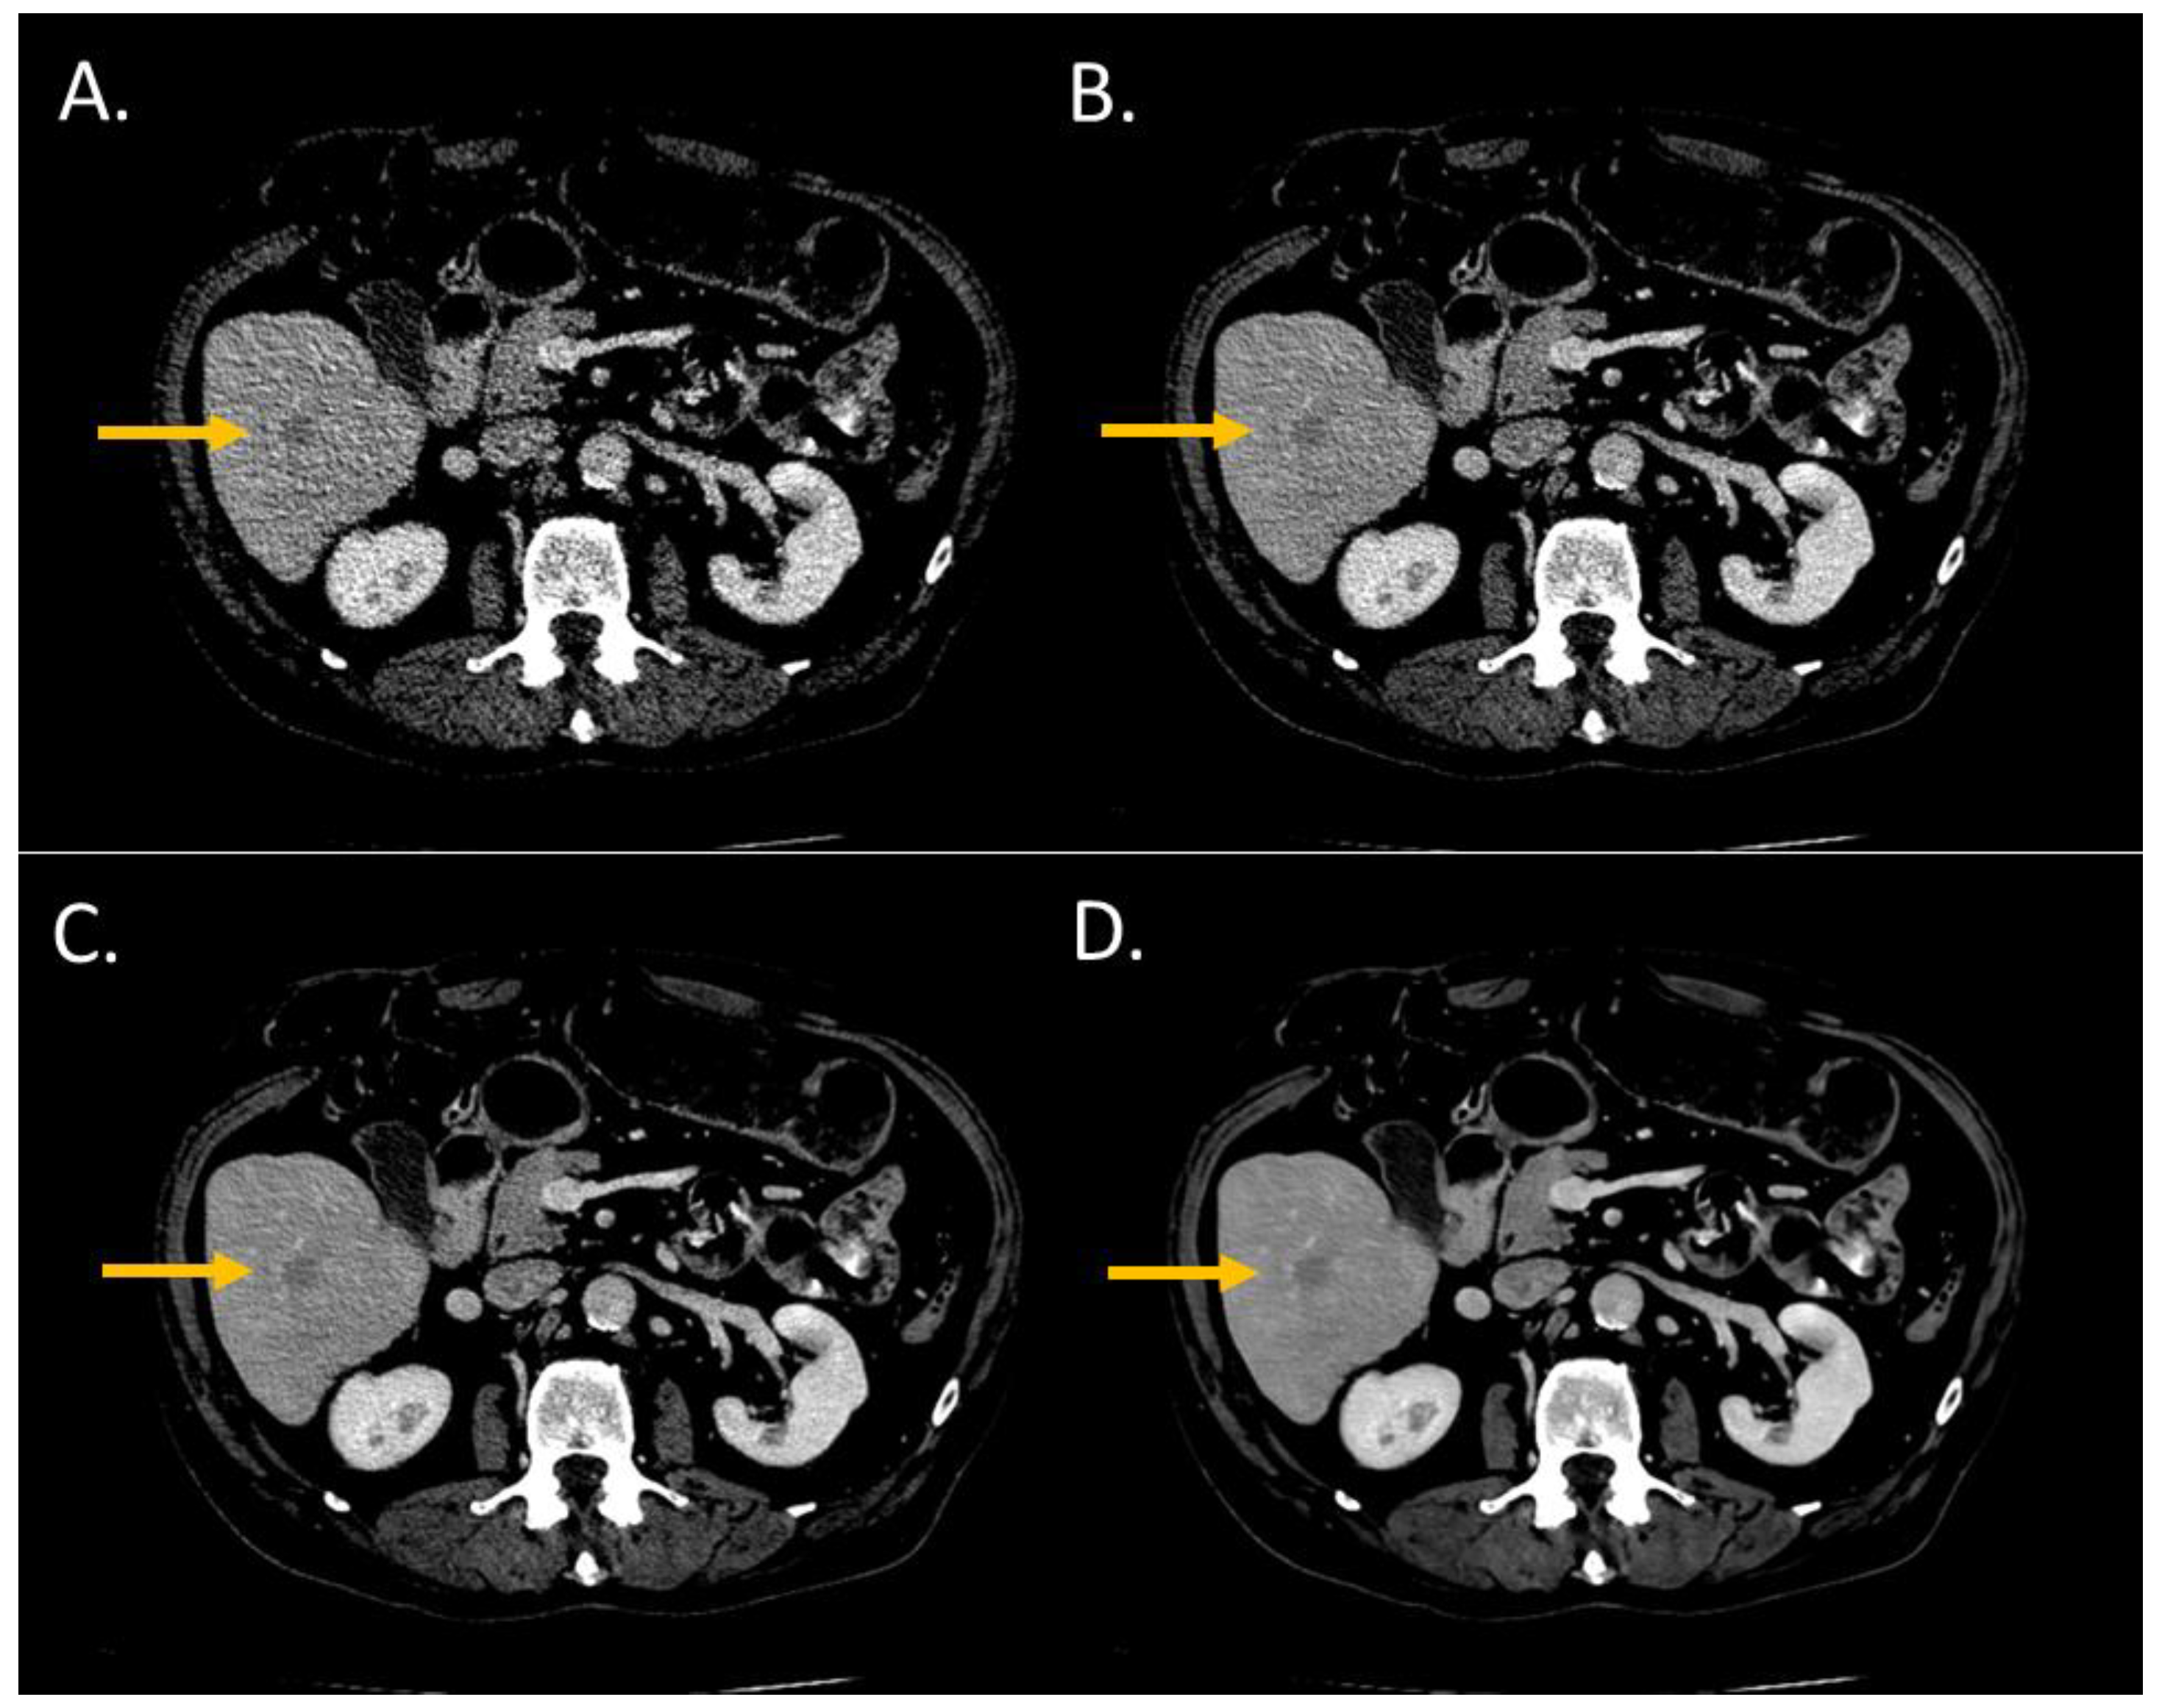

The conspicuity score significantly increased from i4 to the Standard level and from the Standard to the Smoother level (p < 0.05) (Figure 2 and Figure 3). The conspicuity score was ≥4 for 37% with i4, 53% for the Standard, 80% for the Smooth, and 93% for the Smoother level.

Figure 2.

Lesion conspicuity score of liver CT images (WL: 90 HU; WW: 190 HU) of a man (64 years old, SSDE: 6.73 mGy; average scan size 28.9 cm) with colorectal cancer and a liver metastasis of 14.1-mm diameter in the segment VI. (A) iDose4 level 4; lesion conspicuity score: 3; (B) Precise Image, Standard; lesion conspicuity score: 3; (C) Precise Image, Smooth; lesion conspicuity score: 4; (D) Precise Image, Smoother; lesion conspicuity score: 5.